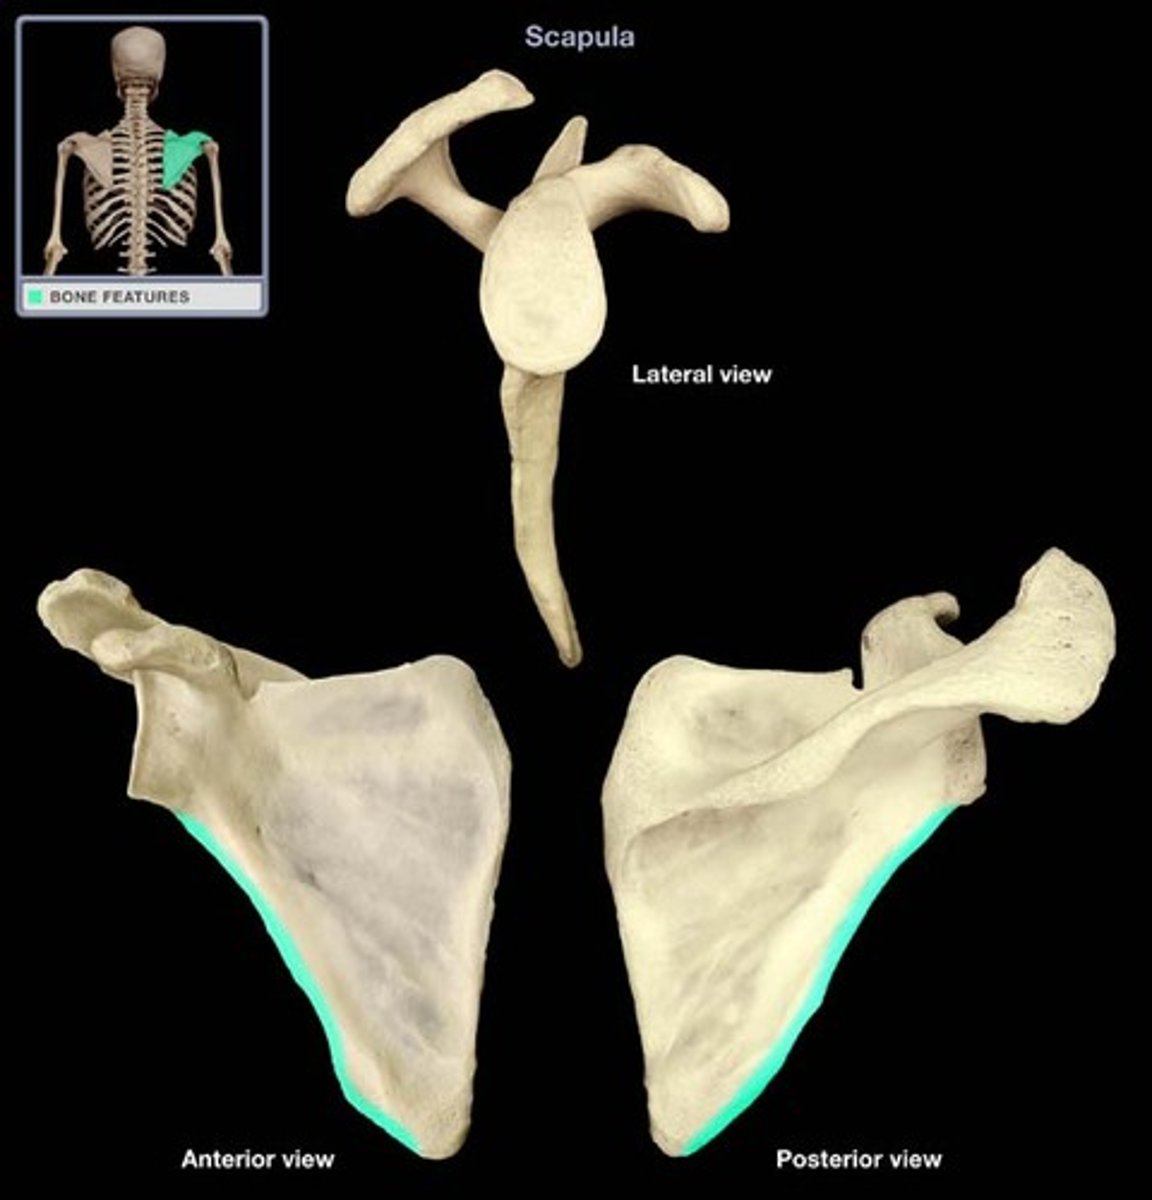

Describe the scapula:

triangular bone

Location of the scapula:

posterior part of the thorax, overlying the 2nd-7th ribs

Scapula articulates with:

humerus (joint) and thoracic wall (physiological scapula-thoracic joint)

Surfaces of the scapula:

- posterior (convex)

- costal (concave)

- lateral

What structures are on the posterior surface of the scapula?

- spine of scapula

- acromion

- supraspinous fossa

- infraspinous fossa

What structure is on the costal surface of the scapula?

subscapular fossa

What structures are on the lateral surface of the scapula?

- glenoid cavity

- coracoid process

- head of scapula

- neck of scapula

- suprascapular notch

Borders of the scapula:

- superior

- lateral

- medial

Where is the superior border of the scapula?

border near the suprascapular notch

Where is the lateral border of the scapula?

border near the humerus

Where is the medial border of the scapula?

border runs parallel to spinous processes of the vertebrae

What are the angles of the scapula?

- superior

- inferior

- lateral

Where is the superior angle of the scapula?

angle at the union of superior and medial borders

Where is the inferior angle of the scapula?

angle at the union of medial and lateral borders

Where is the lateral angle of the scapula?

angle contains the head of the scapula